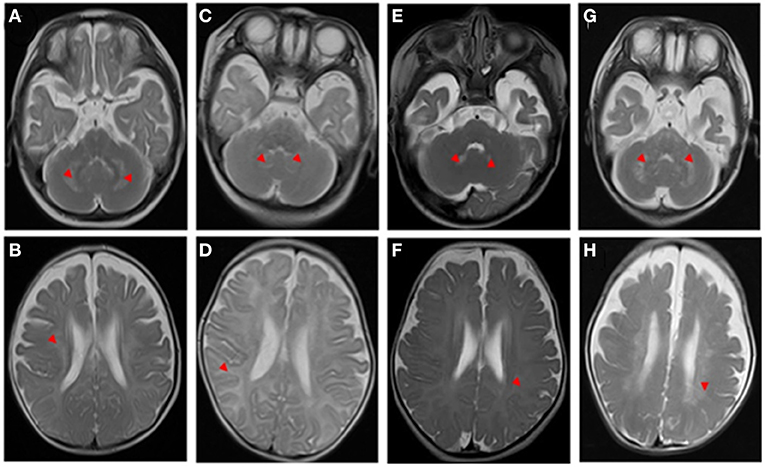

Bệnh Krabbe còn được gọi là loạn dưỡng chất trắng tế bào cầu (globoid cell leukodystrophy), là một rối loạn di truyền hiếm gặp và nghiêm trọng, ảnh hưởng chủ yếu đến hệ thần kinh trung ương. Bệnh này gây ra do sự thiếu hụt enzym galactocerebrosidase (GALC), dẫn đến sự tích tụ của galactolipids trong tế bào thần kinh và các tế bào khác. Sự tích tụ này gây tổn thương cho màng myelin, lớp bảo vệ xung quanh các dây thần kinh, dẫn đến sự thoái hóa của các chức năng thần kinh.

Myelin là lớp bảo vệ xung quanh các sợi thần kinh, giúp tăng tốc độ truyền tín hiệu giữa các tế bào thần kinh. Khi thiếu myelin, các tế bào thần kinh sẽ bị tổn thương nghiêm trọng, dẫn đến cái chết của các tế bào não và các dây thần kinh trong não và các bộ phận khác của cơ thể không thể hoạt động bình thường.